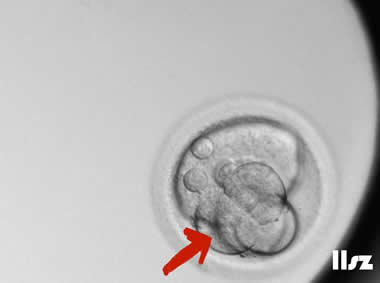

下面视频是胚胎在时差培养箱中培养至D3的整个过程,图片是D3(第68小时)的卵裂期胚胎图,本文D3胚胎评价是以D3时间点图片的形态学为依据,胚胎评级如下:

| Ⅲb级:该枚D3胚胎为7细胞,碎片为10%左右,但由于不具备阶段特异性卵裂模式,因此评级为Ⅲb级。 | |